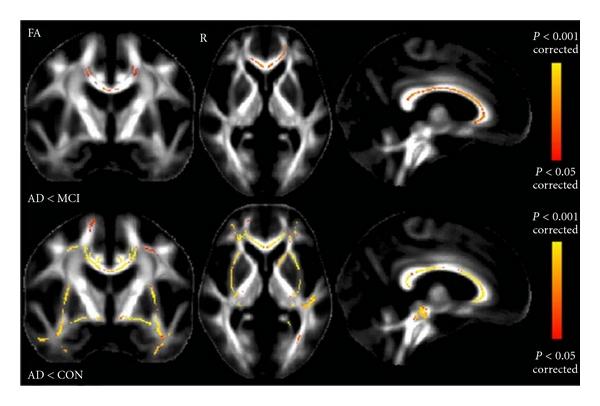

DTI measures in crossing-fibre areas: increased diffusion anisotropy reveals early white matter alteration in MCI and mild Alzheimer's disease.

交叉纤维区域的 DTI 测量:扩散各向异性增加揭示了 MCI 和轻度阿尔茨海默病的早期白质改变。

Neuroimage. 2011 Apr 1;55(3):880-90. doi: 10.1016/j.neuroimage.2010.12.008. Epub 2010 Dec 21.